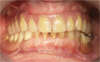

PROTHÈSE MAXILLAIRE SUR SIX IMPLANTS